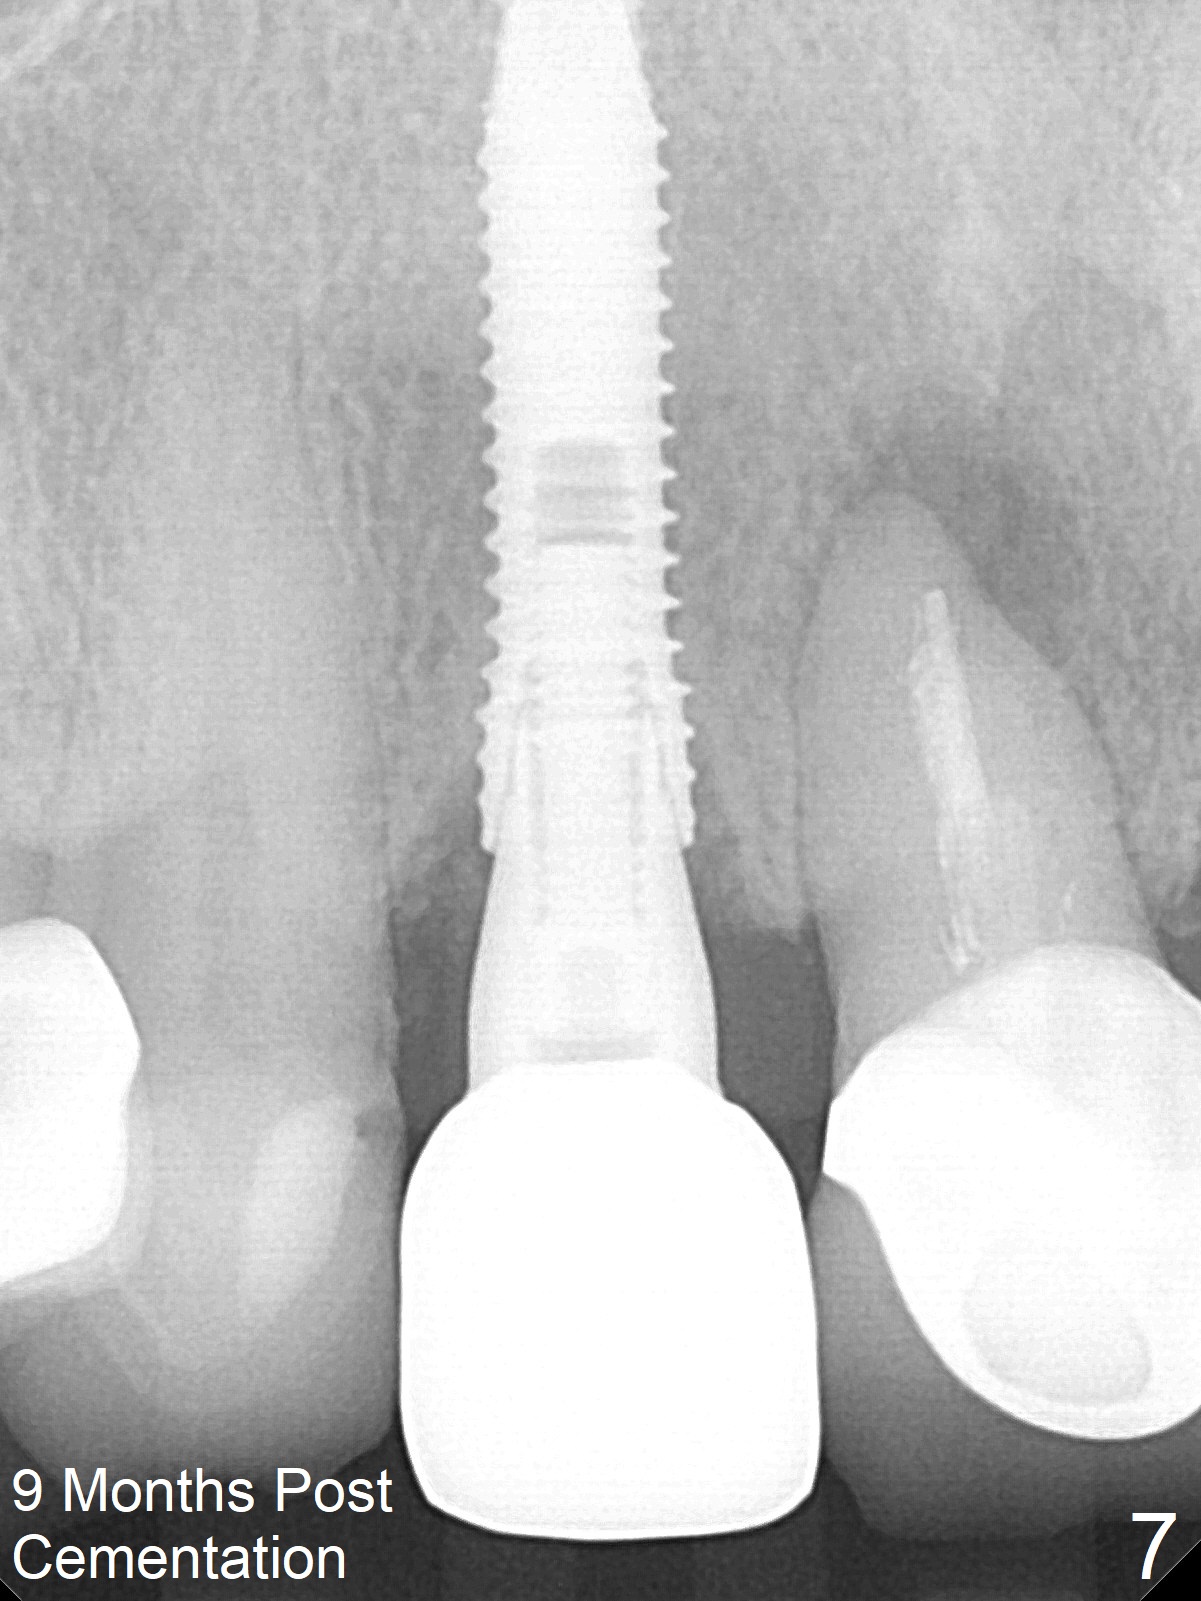

In fact the residual root (Fig.3) is easy to remove. A 3.8x16 mm implant is placed (Fig.4 (with 2 mm buccal gap)) at the level as planned (Fig.2). Insertion torque is acceptable. After placing a 4.5x5(3) mm gold-coated abutment and allograft (Fig.5), an immediate provisional is fabricated (the existing crown is lost). The patient is pleased with the quick, painless procedure.

She returns for impression 4 months postop; the abutment margin is substantially subgingival (Fig.6 arrow). The abutment is changed to 4.5x4(4) mm one before impression. There is no bone resorption 9 months post cementation (Fig.7).